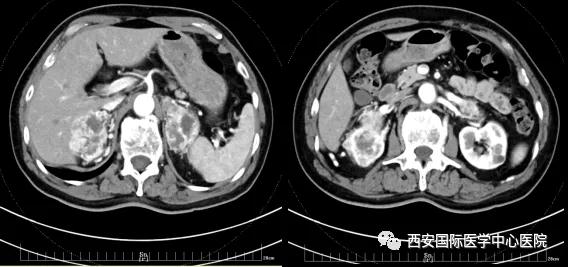

今年七十五歲的患者,來自陜西省商洛市,四月前因腰背部疼痛就診于當(dāng)?shù)蒯t(yī)院,行CT檢查發(fā)現(xiàn)“右腎、雙側(cè)腎上腺占位,前縱膈淋巴結(jié)腫大,雙肺多發(fā)結(jié)節(jié)、胸椎骨質(zhì)破壞,考慮轉(zhuǎn)移瘤”。為進(jìn)一步診斷治療,患者的兒子帶他來到西安某三甲醫(yī)院,查泌尿系CT提示“右腎占位性病變,多考慮腎癌,雙側(cè)腎上腺多發(fā)轉(zhuǎn)移灶,腹膜后多發(fā)腫大淋巴結(jié)”;行穿刺活檢提示“腎透明細(xì)胞癌”;并給予患者口服靶向藥物的治療方案。

自四月份至今,患者一直口服靶向藥物治療(阿昔替尼5mg 2次/日),期間無不良反應(yīng),目前腰背部疼痛癥狀也有所緩解,復(fù)查影像學(xué)資料提示瘤體較前縮小,腫瘤完整切除的可能性明顯提高;而且患者的兒子也是一名外科醫(yī)生,所以他更想為父親完成后續(xù)的手術(shù)治療。

患者一家慕名前來到西安國際醫(yī)學(xué)中心醫(yī)院找到楊增悅教授。楊增悅教授仔細(xì)看完患者的之前的影像學(xué)及病理資料后,診斷為:右腎透明細(xì)胞癌(T4N1M1);并安排他住院。而后,主管醫(yī)生及時(shí)為他完善了術(shù)前檢查及評估。7月15日,在麻醉手術(shù)中心柴偉主任、王彬榮副主任、李娟護(hù)士長、李瑞剛護(hù)士長及全體麻醉手術(shù)中心團(tuán)隊(duì)的有力保障下,成功完成了這臺“大”手術(shù)。

手術(shù)由楊增悅教授主持,舒濤主治醫(yī)師、王東主治醫(yī)師主刀,黃怡醫(yī)師、王平醫(yī)師協(xié)助完成。由于第四代達(dá)芬奇機(jī)器人更加靈活和精準(zhǔn)的特性,手術(shù)全程順利,尤其是完全精準(zhǔn)的“解鎖”了右腎動脈和右腎靜脈的數(shù)十根交互纏繞的分支血管。術(shù)后患者麻醉恢復(fù)后生命體征平穩(wěn),順利返回泌尿外科普通病區(qū)進(jìn)一步康復(fù)。